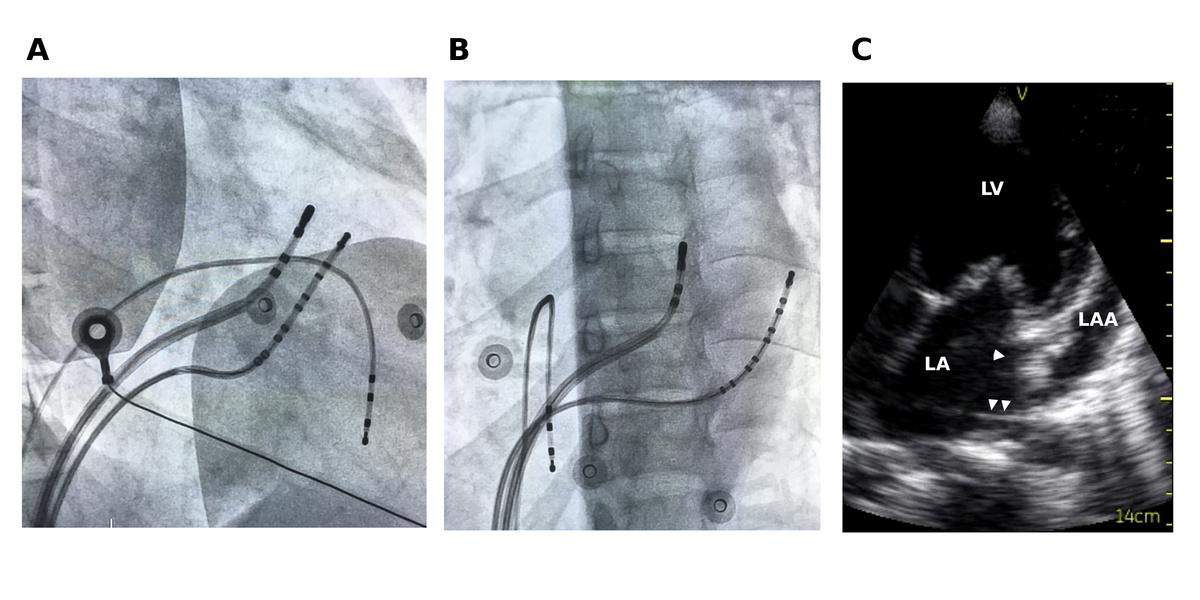

Female with left sided AP

fig1.jpg

A-V separated in CS

fig2.jpg

LAA pathway

fig3.jpg